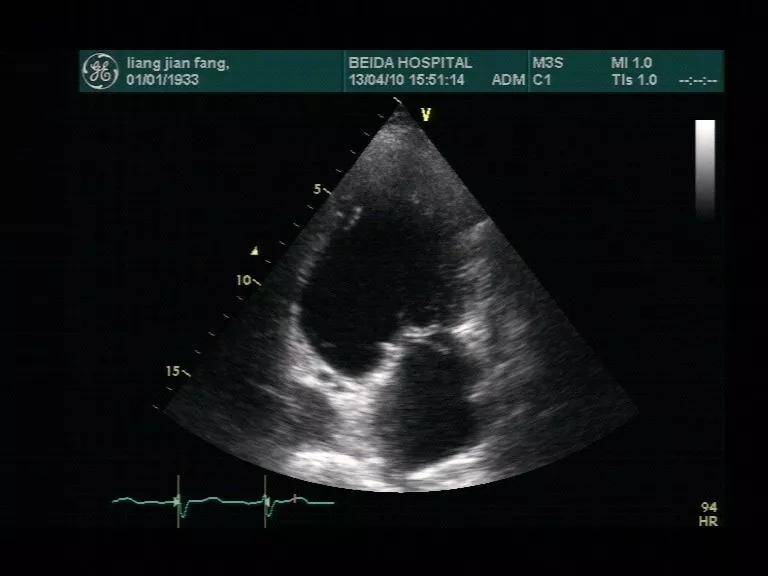

心肌梗塞的超声表现

原创华医心诚医生集团专家杨颖:冠心病超声诊断之心梗并发症